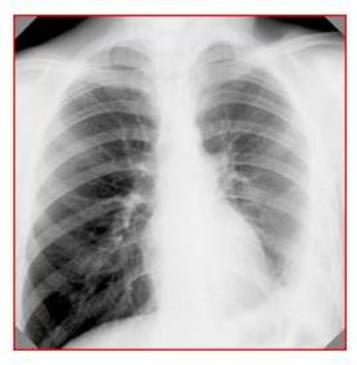

Рентгенологически: очаговая диссеминация по всем лѐгочным полям с обеих сторон, преимущественно в верхних и средних отделах. Контуры очагов нечѐткие, очаги сливаются в фокусные тени, с участками просветления.

Иммунодиагностика: проба Манту 2 ТЕ – папула 12 мм, Диаскинтест – папула 10

мм.

Исследование мокроты на МБТ микроскопически – отр. Посев методом BACTEC - рост МБТ, устойчивых к рифампицину и изониазиду.